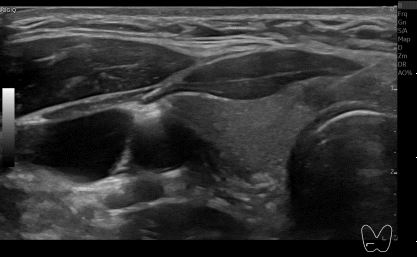

상기환자 외부건진이상소견 정밀검사위해 내원하신 30대중반 여성분으로

의심스러운 갑상선 협부 결절 세포검사 진행후 갑상선암으로 진단되었습니다